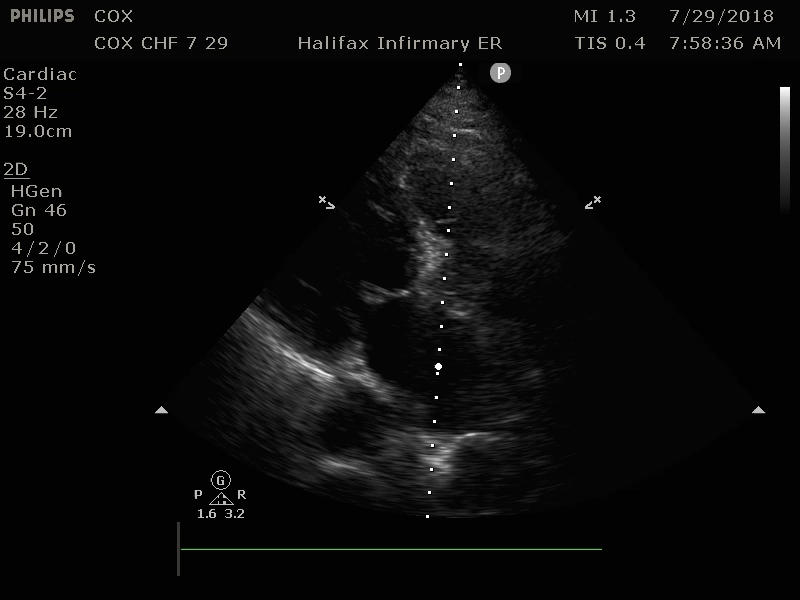

For your patient, your attending physician shows you multiple bilateral lung views, and parasternal long axis (PSL) and apical four chamber (a4C) cardiac views, and explains their significance in making a diagnosis of CHF. (Image 3-6).

Image 5: PSL, Dilated Left Ventricle with poor contraction and poor mitral valve excursion suggesting diminished Ejection Fraction (EF) Original contribution by author, C. Cox. CC BY-SA 3.0 (http://creativecommons.org/licenses/by-sa/3.0

Image 6: a4C, Dilated Left Ventricle with poor contraction and Mitral valve with poor excursion suggesting diminished EF Original contribution by author, C. Cox. CC BY-SA 3.0 (http://creativecommons.org/licenses/by-sa/3.0)

Your attending states that your patient has qualitatively diminished heart function and bilateral interstitial edema. As demonstrated at the bedside, she has B-lines in greater that 2 thoracic quadrants bilaterally which suggests a cardiac source of pulmonary edema. (Sensitivity 97%, Specificity 95%)